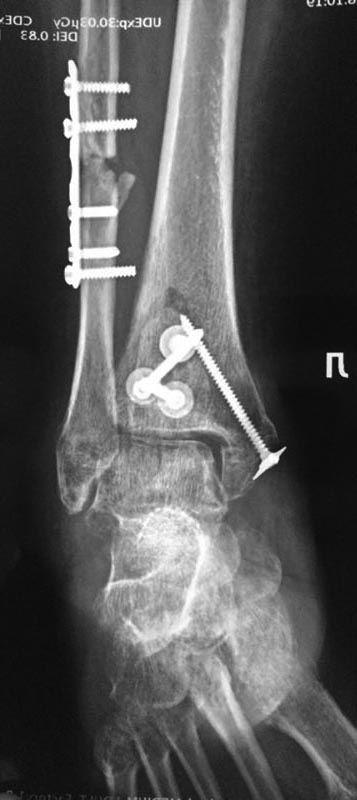

А вот такую задачку нам задали друзья с севера. Операция в мае этого

года. На данный момент пациент опереться на конечность не может.

Возраст: за 50. Движений в голеностопном суставе практически нет ( в

пределах 10-15 градусов) суставы стопы функционируют. Умеренная

контрактура. Ходит с костылями, приступает на ногу. Нагрузка не по оси.

Внешний вид: застарелый отек.

Да, и забыл отметить. Обратите внимание на синтез заднего края. Доступ с

отсечением ахилла